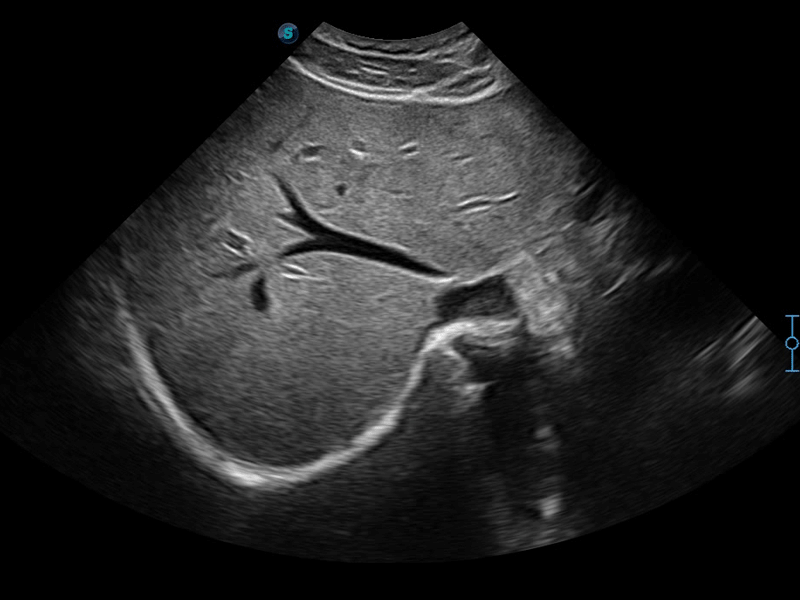

临床图像

SR Flow高分辨率血流成像

高分辨率血流成像技术提高了对低速血流信号的检测能力。在提高空间分辨率的同时,也克服了血流外溢现象,为用户提供更加真实的血流动力学信息。